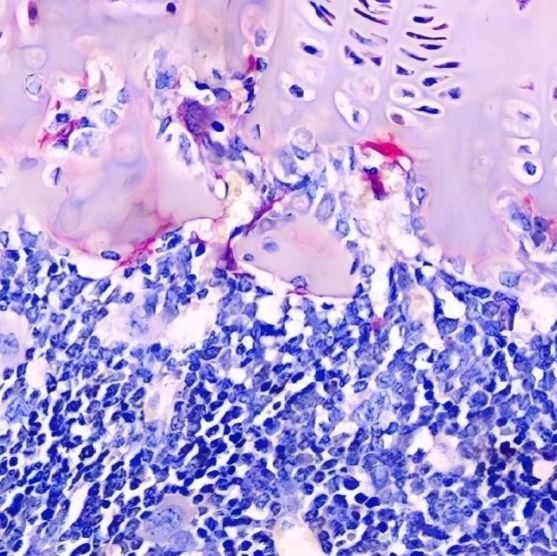

抗酒石酸酸性磷酸酶染色,又称Trap染色,是用于检测骨、骨细胞中破骨细胞的染色,使破骨细胞呈红色,细胞核浅蓝色,用以显示破骨细胞的分布及数量变化

破骨细胞呈酒红色或浅红色,细胞核呈浅蓝色